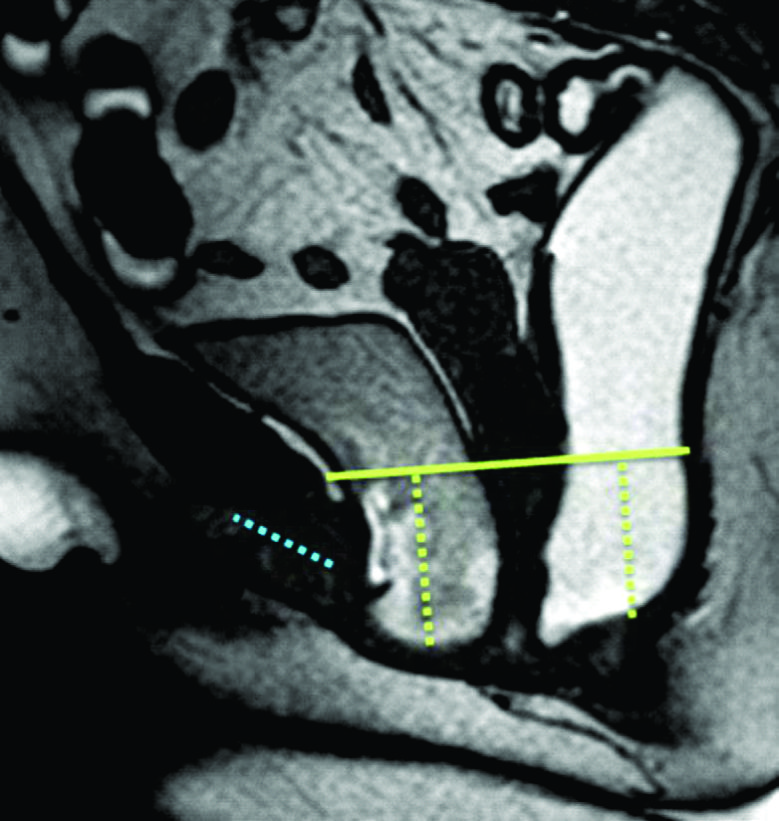

Figura 1

Evaluación anatómica. Líneas de referencia usadas para la valoración de la debilidad del piso pélvico. Imágenes potenciadas en T2 de alta resolución en el plano sagital a nivel de la línea media de una mujer durante el reposo. Recto distendido con gel ecográfico tibio. El útero no es bien visualizado dada su situación para mediana. A) PCL: Línea pubo-coccígea (línea continua). B) MLP: Línea media púbica (línea continua). Para evaluar el prolapso de los órganos pélvicos se trazan líneas perpendiculares desde los puntos de referencia anatómicos en los compartimentos anterior, medio y posterior hasta la línea PCL y/o MLP.

Figura 2

Líneas de referencia. Imagen de la línea media potenciada en T2 en el plano sagital, durante el reposo. Se trazaron la línea PCL (línea continua azul), línea H (línea punteada naranja) y línea M (línea punteada celeste). El músculo puborectal se topografía inmediatamente por detrás de la unión ano-rectal y el plano del elevador es paralelo a la línea PCL.

La valoración del piso pélvico se hace mediante la valoración morfológica, el sistema HMO y el ángulo ano rectal (Ver figuras 1, 2 y 3) (1)

La valoración morfológica se realiza con secuencias potenciadas en T2 de alta resolución, que permiten un estudio anatómico detallado de los órganos de la pelvis. El sistema HMO constituye un método estandarizado creado para caracterizar y documentar el prolapso y relajación del piso pélvico, que se basa en el trazado de tres líneas fundamentales.

La línea pubococcígea (PCL) se extiende desde el borde inferior del pubis a la última articulación coccígea y representa el nivel de piso pélvico, constituyendo la línea de referencia a partir de la cual se miden los prolapsos, tanto en reposo como en Valsalva.

La línea H se traza desde el borde inferior del pubis hasta la pared posterior del recto a la altura de la unión ano rectal, representando el diámetro anteroposterior del hiato urogenital, con un valor normal menor a 6 cm (Ver figuras 4).

La línea M es perpendicular a la PCL a nivel del sector más posterior de la línea H y representa el descenso del hiato del elevador, con un valor normal menor a 2 cm. El ángulo ano rectal es el ángulo entre el eje central del canal anal y la pared posterior del recto, con un valor normal entre 108º y 127º y una variación de hasta 15º en Valsalva.

Se describe una línea adicional llamada línea media púbica (MPL) que se traza caudalmente siguiendo el eje mayor de la sínfisis del pubis. Esta línea corresponde al nivel del himen vaginal, el cual es utilizado históricamente como punto de referencia para la valoración clínica. 12-13